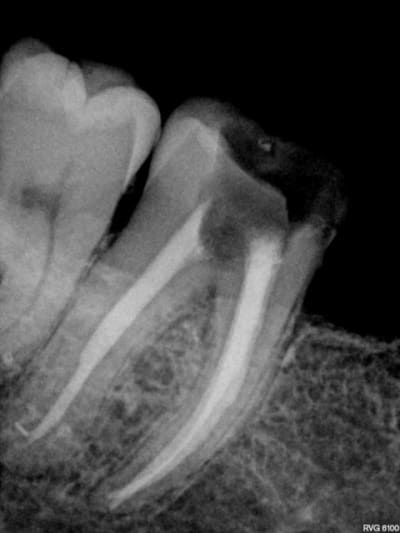

Ton endo était pas mal.

C'est étonnant que le matériau d'obturation qui était dense en 2011 se soit dégradé à ce point et si vite.

Il est possible qu'il y ait autre chose (perfo latérale un peu en dessous du plancher, fracture de la racine MV).

Pour moi jusqu'à preuve du contraire c'est un alea.

Par contre à ta place je ne contesterais rien du tout, t'es en tort à 300%. J'espère pour toi que toutes tes endos ne sont pas comme ça. Certains me diront que je suis sévère blablabla "ça t'es jamais arrivé de rater" etc, mais en sortant de la fac faire ça je trouve ça honteux.

Mets au moins un cône un minimum calibré. La gutta ne "disparaît" pas.

il peut la reprendre comme il veut l'endo , elle parait cuite la dent. ça a l'air multifactoriel ce truc avec une tres tres grosse composante occlusale .

Completement d'accord avec enlaye pour le multifactoriel ;l'infection est inter radiculaire , suite a une recession parodontale importante ,il suffit de voir la radio. Le retraitement (avec ou sans digue, :-)) est bien, mais ne donnera rien de plus!

Pour l'endo, c'est vrai que la disparition du matériaux d'obturation ne plaide pas en la faveur de notre jeune confrère.

La radio post-op du 15/11/2011 semble montrer la présence de cône de gutta dépassant coronairement . L'erreur ne viendrait-elle pas d'une empreinte de l'ic dans la foulée .

la préparation a retiré les cônes laissant le ciment endodontique.

Concernant une lésion interradiculaire je suis dubitatif en voyant uniquement cette radio .

Je vais peut-être dire une connerie mais la dernière radio semble avoir été prise pendant le rtr après desobturation non ?

C'est le titulaire qui t'a envoyé la dernière radio ?